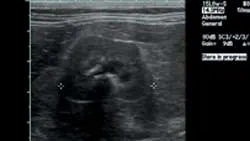

ImagingAbdominal radiographs showed small irregular kidneys (Figure 1, right: Radiograph of the right lateral abdomen. The kidneys are small and irregularly shaped. Mineral densities are visible in the left kidney. View larger image), and irregular margins were evident in ultrasound imaging (Figure 2, below: Ultrasound of the left kidney demonstrating irregular margins. View larger image).